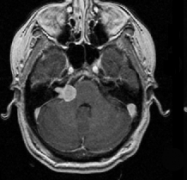

听神经瘤是脑内桥小脑角区(CPA)比较常见的脑肿瘤,中老年人多见。听神经瘤发生于前庭神经雪旺氏细胞鞘,因为面神经、听神经、前庭上和前庭下神经组...

当耳鸣患者去耳鼻喉科寻求帮助时,诊断的一步通常是听力学检查和核磁共振成像(MRI)。磁共振检查是为了排除听觉神经瘤或其他器质性耳鸣的可能性...